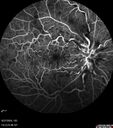

Central Retinal Vein Occlusion - Non-Ischemic - Excellent Outcome17 views57 year old man The right eye has had vision loss for about 3 weeks. He woke up with vision loss.

Medical Hx: HIV . Diabetes Mellitus (since 2014). Thyroid Disease.

Systemic Meds: gemboya. Metformin Hydrochloride. trulicity. losartan. vesepa. Synthroid .

VA OD: sc20/160 OS: sc20/20

TP: OD:14 OS:14

Treated with Avastin

VA 6 weeks later 20/32 – dry one shot.

Missed follow-up after second treatment and came 5 months later with good vision and no macular edemaAug 17, 2025